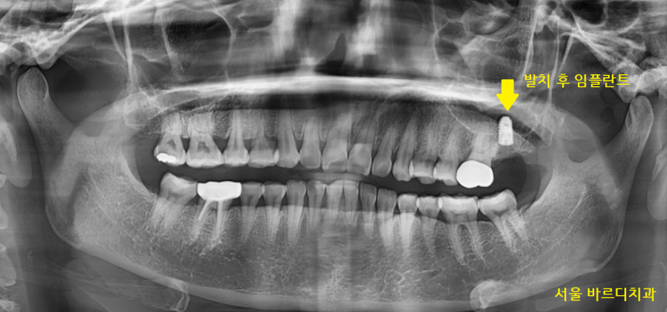

240213

그 이후 과정은 같습니다.

임플란트와 뼈가 단단하게 붙으면

기둥을 세우고 머리를 제작

240318

어금니 뿌리 쪼개짐으로 발치하셨지만

튼튼하게 사용하실 수 있도록

임플란트 심어드렸습니다!!